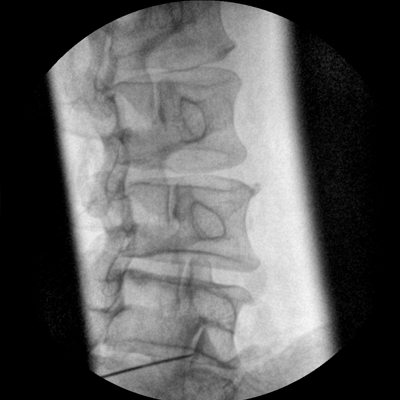

Clinical picture

臨床圖片